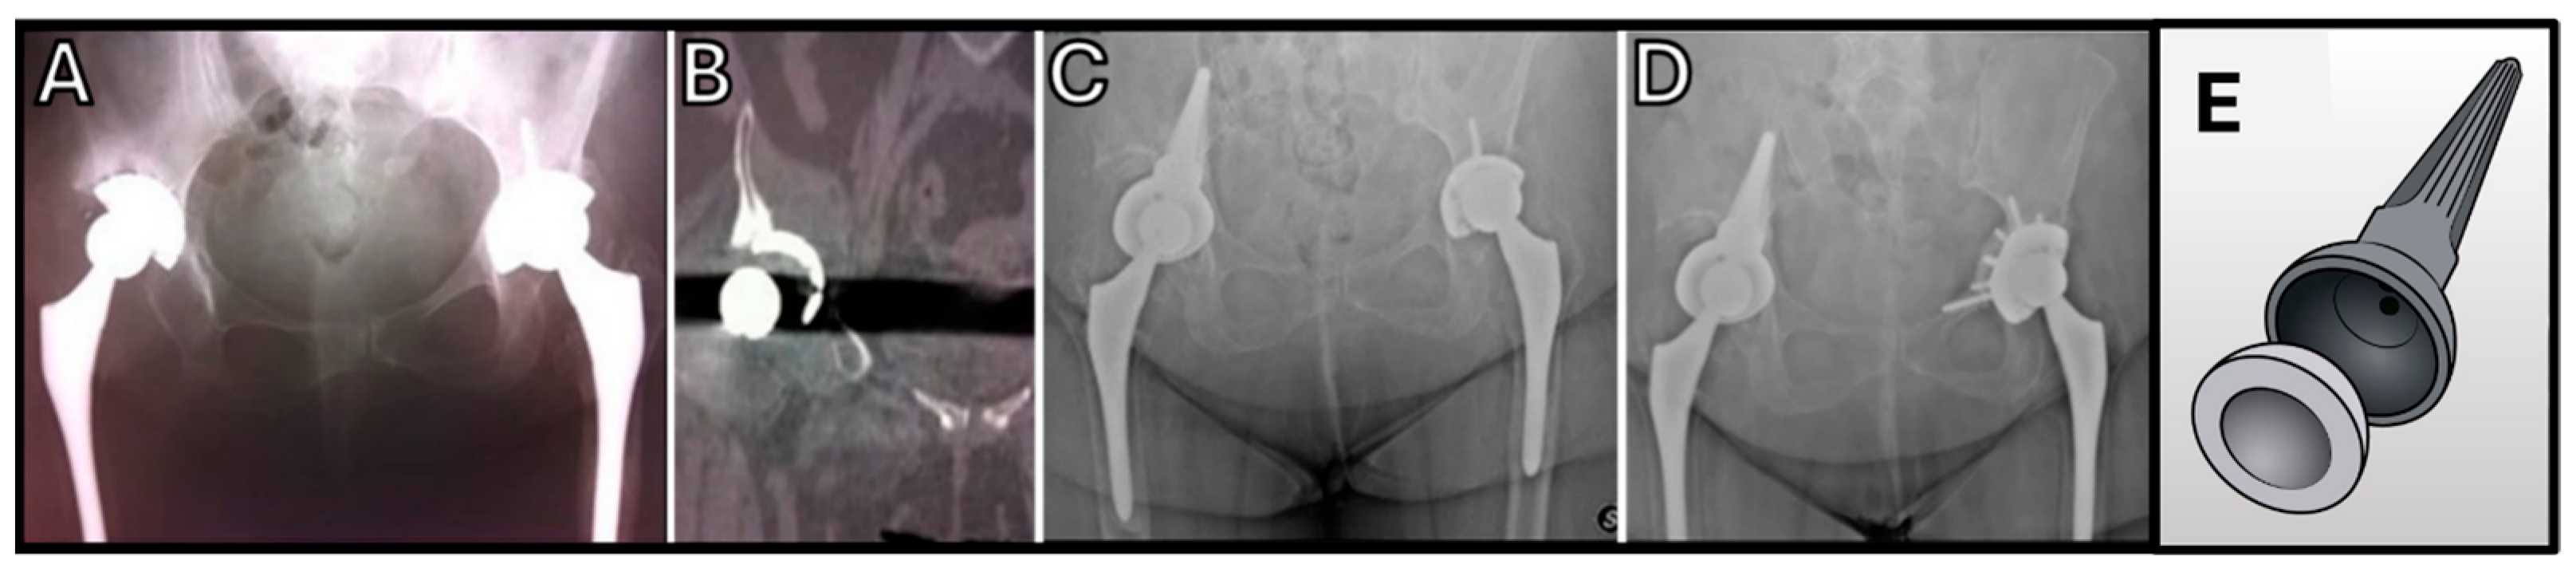

- Issa, S.-P.; Biau, D.; Leclerc, P.; Babinet, A.; Hamadouche, M.; Anract, P. Stemmed acetabular cup as a salvage implant for revision total hip arthroplasty with Paprosky type IIIA and IIIB acetabular bone loss. Orthop. Traumatol. Surg. Res. OTSR 2020, 106, 589–596. [Google Scholar] [CrossRef] [PubMed]

| Issa et al. 2020 [63] | Severe acetabular deficiency | 14 patients | Integra Cup (Lepine) | 48.8 Months (±23.4 Mos) | Postoperative complications: 18.8% infections; 6.7% dislocations; 12.5% loosening; 18.8% implant removed. |